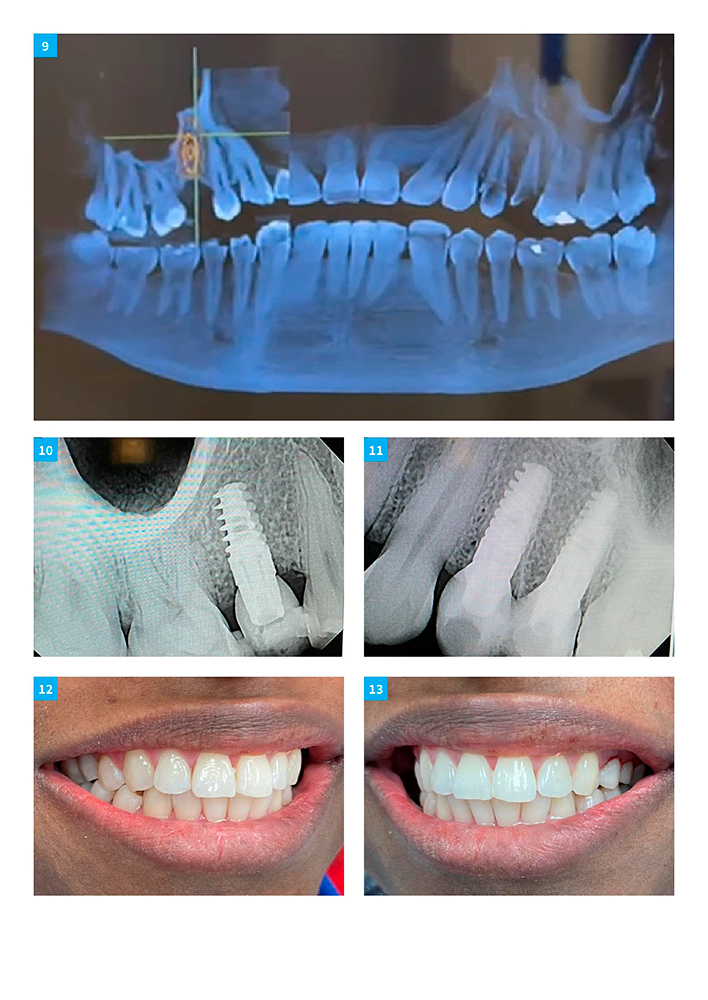

Dr Zuzel Trujillo Posterior Teeth Replacement With Implants On Both Sides Of Maxilla